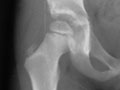

• Legg-Calve-Perthes disease. This condition is caused by decreased blood flow to the head of the femur which affects the bone as seen on the X-ray and an MRI of a child with this problem.